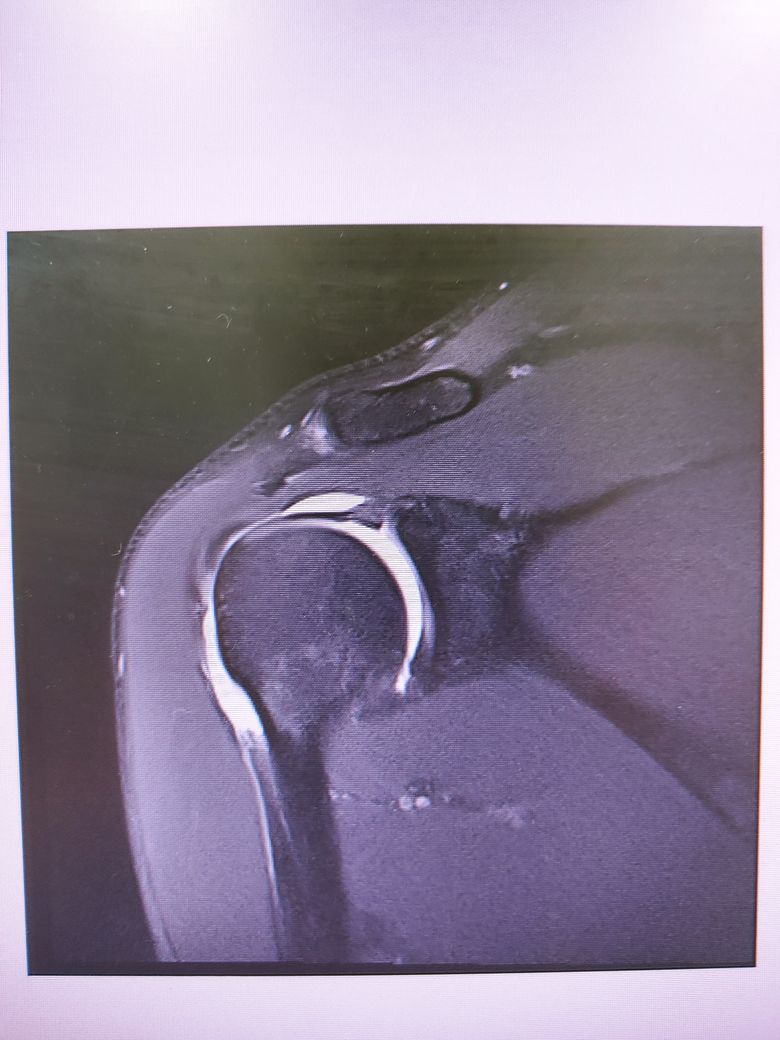

어깨 mri 판독 가능할런지요?

족구 중 다른 사람과 부딛혀 넘어지는데

상대가 넘어지지 말라고 팔을 잡아주었습니다.

그런데 무방비 상태에서 팔이 당기다보니

어깨에서 소리가나더라구요.

세달째 통증이 지속되어

병원가서 Mri는 찍고 아직 진단은 받지 못했습니다..

회전근개 부분파열으로 볼 수 있나요..?

어깨 MRI는 수십장 이상의 사진이 연속적으로 찍히는 것으로 위 사진들만으로는 정확한 판별이 어렵겠습니다.

나와있는 cut에는 큰 문제가 없어보입니다.

현재 사진상으로 회전근개 파열을 확실히 진단하기는 힘들것 같습니다.

하지만 현재 MRI상 어깨 관절내에 밝게 보이는 곳은 물 또는 혈액등으로, 활액막염 등으로 인해 염증성 변화가 일어난 것으로 보입니다.

이는 소염진통제 등을 드시면서 경과관찰을 해보시는 것이 좋겠으며, 현재 사진만으로는 회전근개 파열을 단정하기 어려우므로 정확한 진단에 대해서는 해당병원에서 설명을 들으시는 것이 좋겠습니다.